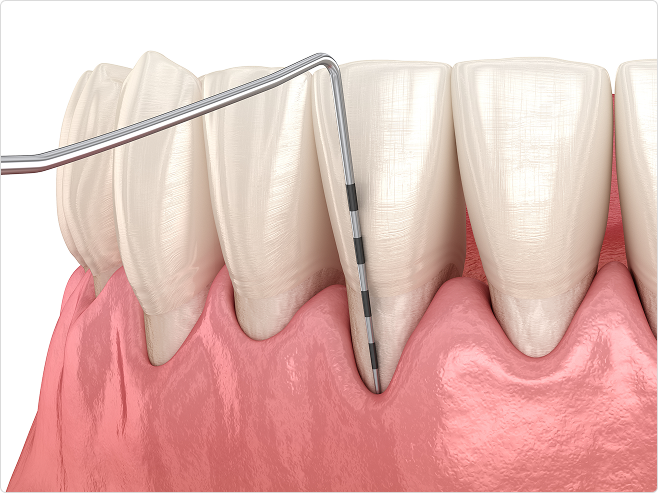

비수술적 잇몸 치료 - 치주 소파술

잇몸 아래 치아 뿌리 부위까지 치석이 내려간 경우, 국소마취 또는 수면마취 하에

‘큐렛(curette)’이라는 전용 기구로 치석과 염증 조직을 정밀하게 제거합니다.